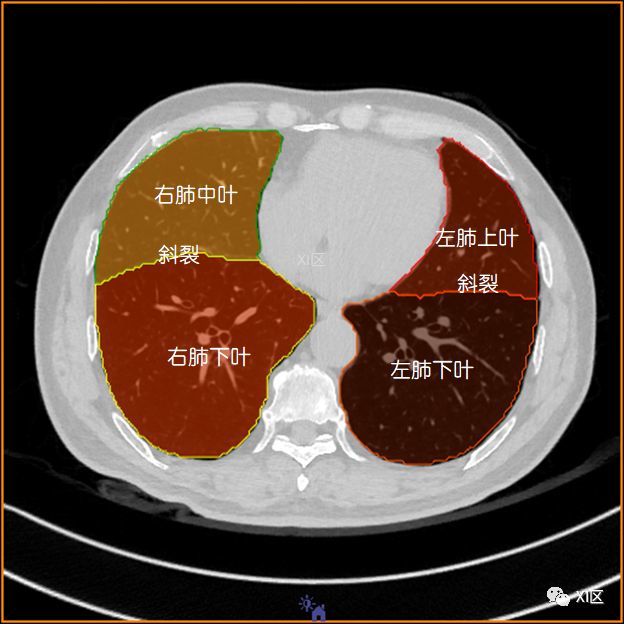

肺的解剖与分段

肺部解剖与分段

肺段ct彩色_解剖图